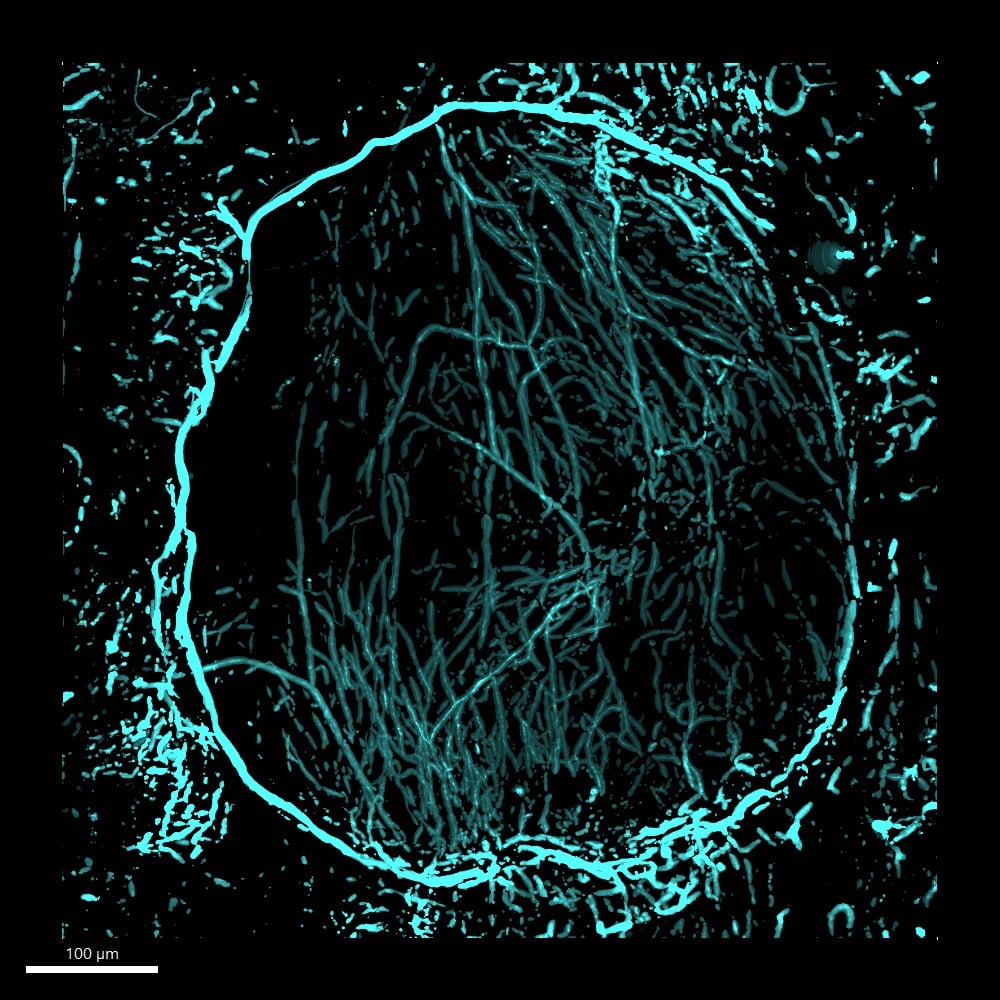

Above image: Nerves in a non-healing skull defect four weeks after injury (Image Credit: The Grayson Laboratory)

The tiny nerves inside your bones—which are vital for maintaining bone strength and healing fractures—are finally being brought to light. These delicate structures have historically been incredibly hard to see and study, but Johns Hopkins University researchers have cracked this imaging challenge.

The team created an automated 3D method using artificial intelligence to precisely map the peripheral nerve network in dense bone tissue. Described in the journal Bone Reports, their machine learning-powered discovery is set to accelerate the search for new treatments for fractures and degenerative diseases like osteoporosis.

To achieve this, the team developed a three-step system. First, a high-powered camera captures detailed 3D pictures of the bone. The main innovation was integrating a machine learning (ML) program called Ilastik®. The second step utilizes machine learning to sift through dense bone tissue to map and isolate the delicate nerves. This process effectively strips away all the distracting background noise, which is exacerbated by inflammatory conditions. Finally, a separate tool named Imaris analyzes this clean data to precisely calculate structural measurements such as nerve density.

The method was successfully tested across multiple bone types, including the skull, the long bones in the foot (metatarsal bone), and the knee.

In ongoing studies, the method was applied to samples of injured skull bone to map nerves, blood vessels, and bone-forming cells after injury. The team hopes the detailed data from these nerve maps will finally help solve the mystery of why some bone injuries heal and others don’t.